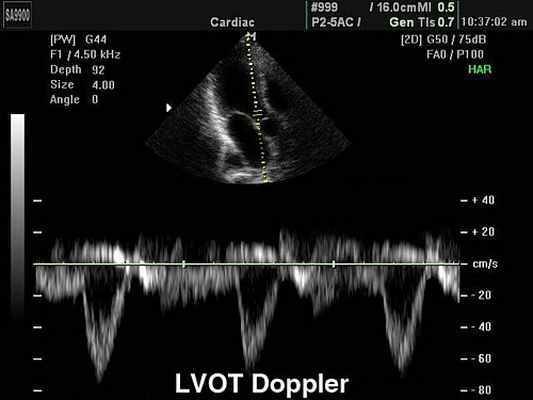

Так, например, эхокардиография с допплерометрией и цветным допплеровским картированием (ЦДК), которая является сочетанием 2D и М-режимов с допплерометрией, очень полезна при оценке митрального стеноза. Первые два способа визуализации позволяют заподозрить кальцификацию клапана (аномальное движение его створок).

Допплерометрия демонстрирует при этой патологии повышенную скорость кровотока (признак сужения) и может быть использована для оценки «эффективной площади отверстия» (степени выраженности стеноза).

Суть метода допплерографии

Допплерография – это метод УЗИ диагностики, основанный на эффекте Доплера: изменение частоты УЗ-волн, отраженных от движущихся эритроцитов. Допплеровский сдвиг частоты позволяет судить о скорости и направлении кровотока. В результате передачи серии ультразвуковых импульсов в ткани на экране монитора получают график, демонстрирующий изменение скорости кровотока с течением времени на заданной глубине (допплеровский спектр или частотный спектр эхо-сигналов, поступающих от кровотока).